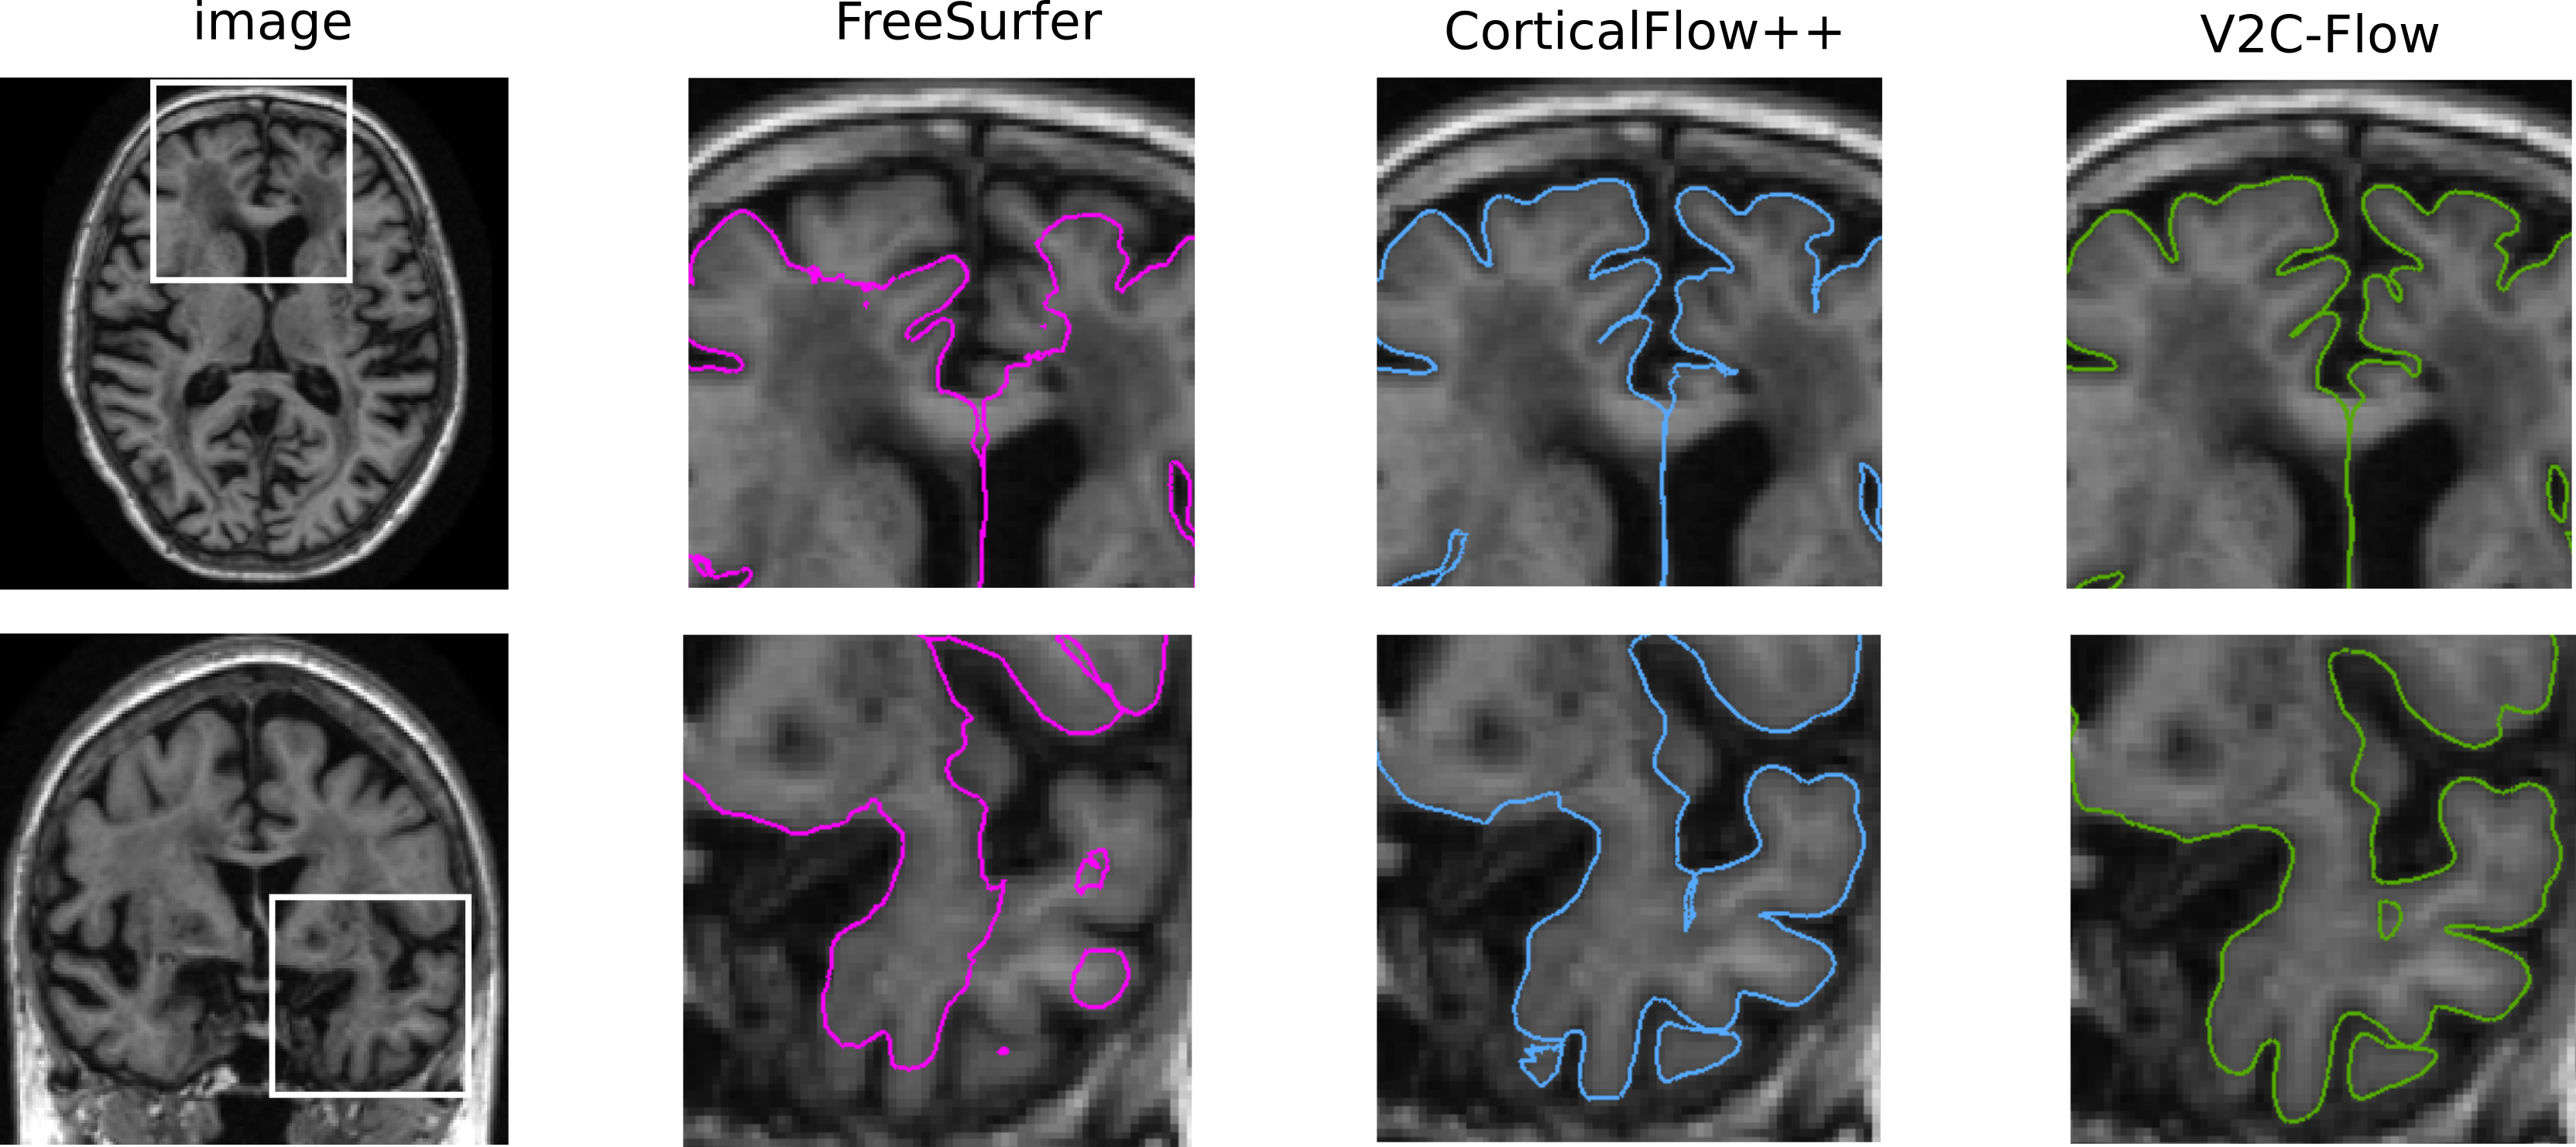

Refer to caption

Fig. 3: V2C-Flow yields accurate and smooth surfaces while alternative methods introduce artifacts in this sample from the ADNI test set. The required inference time is measured in seconds (s) or hours (h) for the reconstruction of the four cortical surfaces of one subject on an Nvidia A6000 GPU for DL-based methods and on a single CPU for FreeSurfer (v7.2).

In comparison to other DL-based methods for cortical surface reconstruction, V2C-Flow performs comparable to the best alternative methods, i.e., CorticalFlow++ (CF++) and CortexODE (CODE), with V2C-Flow being in the forefront on both, WM and pial, surfaces. We attribute the highest accuracy of CF++, CODE, and V2C-Flow to the continuous-time deformation process that they have in common. In terms of training time, though, V2C-Flow is about 10 times faster than CF++, taking three days instead of four weeks. The long training time in CF++ is probably due to the compute-intensive ODE-solver (Runge-Kutta method with 30 integration steps) and the separate modeling of the deformation fields (three UNets per surface). CODE, on the other hand, is slower in terms of inference time (14s vs. 1.6s in V2C-Flow, cf. fig. 3) due to the sequential segmentation and mesh extraction approach and does not come with point correspondences to a template. Other DL-based baseline methods, either template-based (Vox2Cortex [2] (V2C), CorticalFlow [29] (CF), TopoFit [21]) or SDF-based (DeepCSR [50]), are clearly outperformed in terms of surface accuracy. Supported by the observations from Figure 3 and Supplementary Table 2, we further argue that the separate modeling of surfaces in CF/CF++ and TopoFit bears the risk of creating many anatomically implausible intersections between WM and pial surfaces. Instead, the joint modeling in V2C-Flow reduces the number of intersecting WM and pial surfaces. Further artifacts of existing methods like intersections with the skull (CF, CF++) and distorted surfaces (DeepCSR, FreeSurfer) are also alleviated in V2C-Flow as shown in Figure 3.